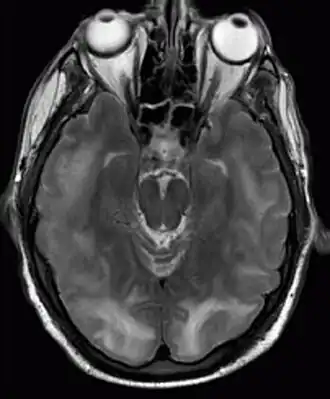

Resonancia magnética nuclear en la que son visibles lesiones de encefalopatía posterior reversible. | ||

El síndrome de encefalopatía posterior reversible, también llamado síndrome de leucoencefalopatía posterior reversible (RPLS por sus siglas en inglés), es un trastorno neurológico de inicio brusco que se presenta con dolor de cabeza, disminución del nivel de conciencia, convulsiones, trastornos visuales y déficits neurológicos focales.[1] En las imágenes obtenidas mediante resonancia magnética nuclear de la cabeza, se visualizan áreas de edema cerebral en la sustancia blanca que afecta predominante a las regiones posteriores del cerebro, principalmente al lóbulo parietal y al lóbulo occipital. El pronóstico a largo plazo es bueno, produciéndose por lo general recuperación completa, aunque en ocasiones persisten secuelas irreversibles. La mortalidad es de alrededor del 6%. El cuadro se asocia a diferentes circunstancias, algunas de las más frecuentes son: tratamiento con medicamentos inmunosupresores o quimioterápicos, hipertensión arterial, infecciones graves o sepsis, enfermedades autoinmunes como el lupus eritematoso sistémico y la púrpura trombocitopénica idiopática, insuficiencia renal y preeclampsia. La causa y el mecanismo fisiopatológico que provocan el síndrome no se conocen con exactitud, podría deberse a lesión en el endotelio de los vasos sanguíneos cerebrales por cambios bruscos en la presión arterial, o a la acción de sustancias llamadas citocinas que dañarían el endotelio de la pared de los vasos. [2][3]